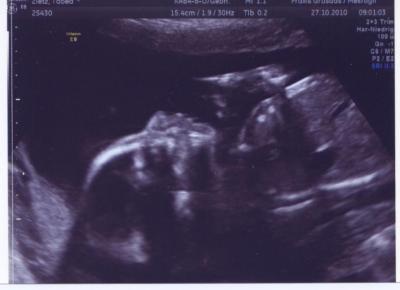

Hier noch ein Bild von der letzten Untersuchung :)

Bild zu Ich hab auch noch ein Foto - Forum für März - Mamis

Oh, was en süßes Foto :-) lg